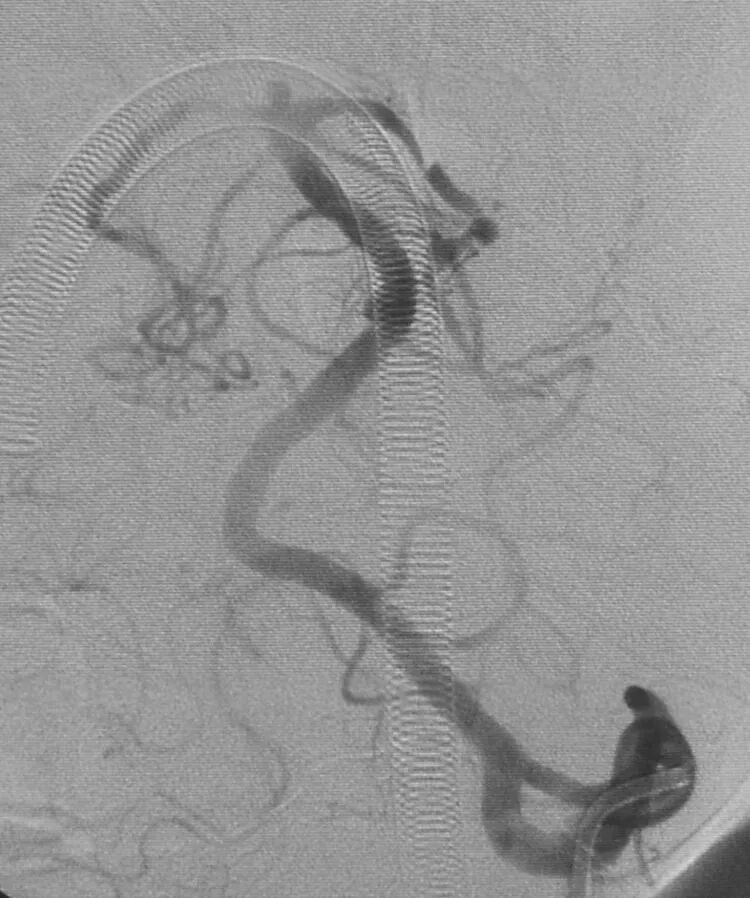

后交通动脉瘤,朝外下方生长,欲把微导管头塑成C形,需塑两个弯儿,第一个弯儿(蓝箭头)顺应动脉瘤体和颈内动脉C1段的成角,第二个弯儿(绿箭头)顺应颈内动脉虹吸弯前膝的弯度,更近心端的弯儿(黑箭头)不用塑形,是微导管在载瘤动脉内的自然成形

栓塞后的工作位造影和蒙片